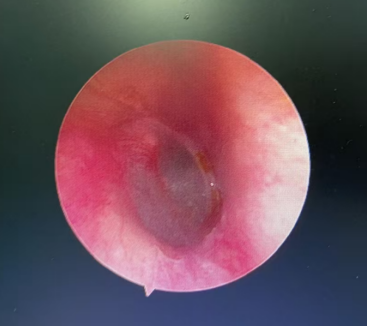

不久后,确认蟑螂已被处死,金先生疼痛暂时缓解,大清早又赶紧去做耳内镜,医生最终用镊子从金先生外耳道取出了指甲盖大小的蟑螂,并为他进行耳道消毒。

取出虫子后